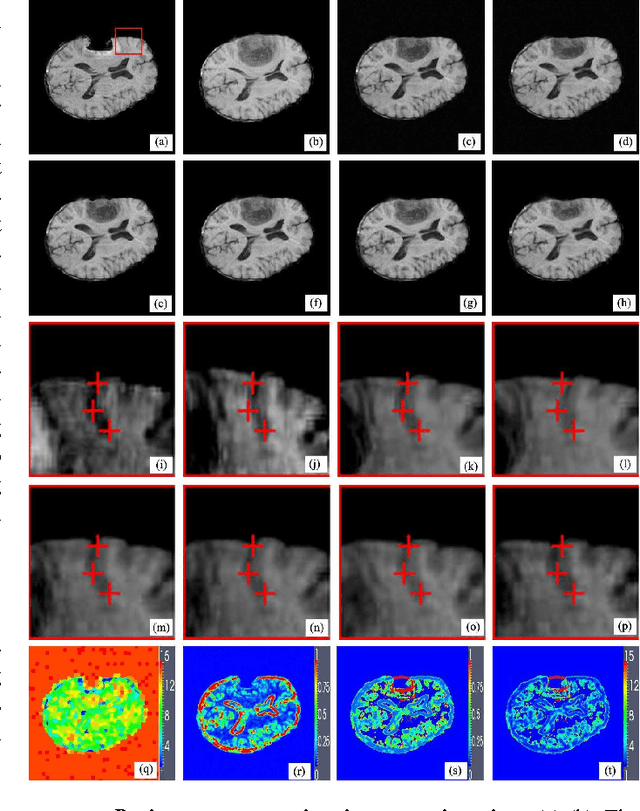

Abstract:For nonrigid image registration, matching the particular structures (or the outliers) that have missing correspondence and/or local large deformations, can be more difficult than matching the common structures with small deformations in the two images. Most existing works depend heavily on the outlier segmentation to remove the outlier effect in the registration. Moreover, these works do not handle simultaneously the missing correspondences and local large deformations. In this paper, we defined the nonrigid image registration as a local adaptive kernel regression which locally reconstruct the moving image's dense deformation vectors from the sparse deformation vectors in the multi-resolution block matching. The kernel function of the kernel regression adapts its shape and orientation to the reference image's structure to gather more deformation vector samples of the same structure for the iterative regression computation, whereby the moving image's local deformations could be compliant with the reference image's local structures. To estimate the local deformations around the outliers, we use joint saliency map that highlights the corresponding saliency structures (called Joint Saliency Structures, JSSs) in the two images to guide the dense deformation reconstruction by emphasizing those JSSs' sparse deformation vectors in the kernel regression. The experimental results demonstrate that by using local JSS adaptive kernel regression, the proposed method achieves almost the best performance in alignment of all challenging image pairs with outlier structures compared with other five state-of-the-art nonrigid registration algorithms.

Abstract:Joint saliency map (JSM) [1] was developed to assign high joint saliency values to the corresponding saliency structures (called Joint Saliency Structures, JSSs) but zero or low joint saliency values to the outliers (or mismatches) that are introduced by missing correspondence or local large deformations between the reference and moving images to be registered. JSM guides the local structure matching in nonrigid registration by emphasizing these JSSs' sparse deformation vectors in adaptive kernel regression of hierarchical sparse deformation vectors for iterative dense deformation reconstruction. By designing an effective superpixel-based local structure scale estimator to compute the reference structure's structure scale, we further propose to determine the scale (the width) of kernels in the adaptive kernel regression through combining the structure scales to JSM-based scales of mismatch between the local saliency structures. Therefore, we can adaptively select the sample size of sparse deformation vectors to reconstruct the dense deformation vectors for accurately matching the every local structures in the two images. The experimental results demonstrate better accuracy of our method in aligning two images with missing correspondence and local large deformation than the state-of-the-art methods.